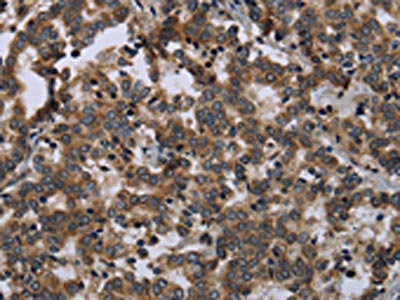

The image on the left is immunohistochemistry of paraffin-embedded Human liver cancer tissue using CSB-PA120525(FGF18 Antibody) at dilution 1/20, on the right is treated with fusion protein. (Original magnification: ×200)